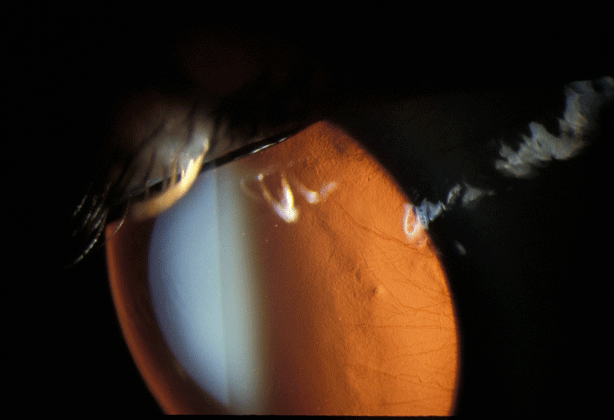

Contact lens related circinate interstitial keratitis with neovasculariztion. Courtesy Joel Sugar, MD